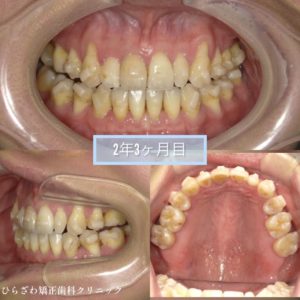

〜2年3カ月目〜

前歯の噛み合わせは完全に閉じましたが、奥歯にまだ隙間がありますね😂

とっても真面目にマウスピースを使用し、舌のトレーニングもして頂いていましたが

元々ある舌癖を治すのは難しいものです、、、

舌が前だけではなく横にも出てくる癖があったため、これまで以上に気をつけて頂きました😵💫